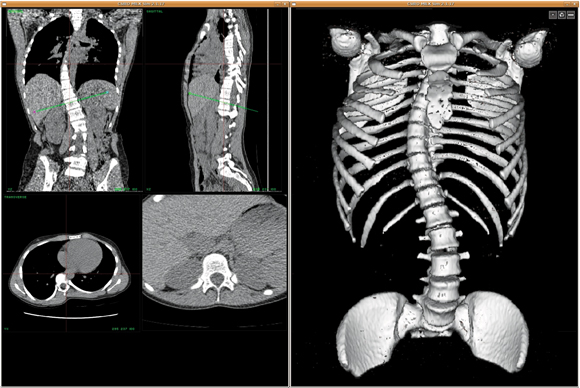

The Australian e-Health Research Centre,1 in collaboration with the Queensland University of Technology’s Paediatric Spine Research Group,2 is developing software for visualisation and manipulation of large, three-dimensional (3D) medical image datasets. The software allows the extraction of anatomical data from individual patients for use in preoperative planning. State-of-the-art computer technology makes it possible to slice through the image dataset at any angle, or manipulate 3D representations of the data instantly.